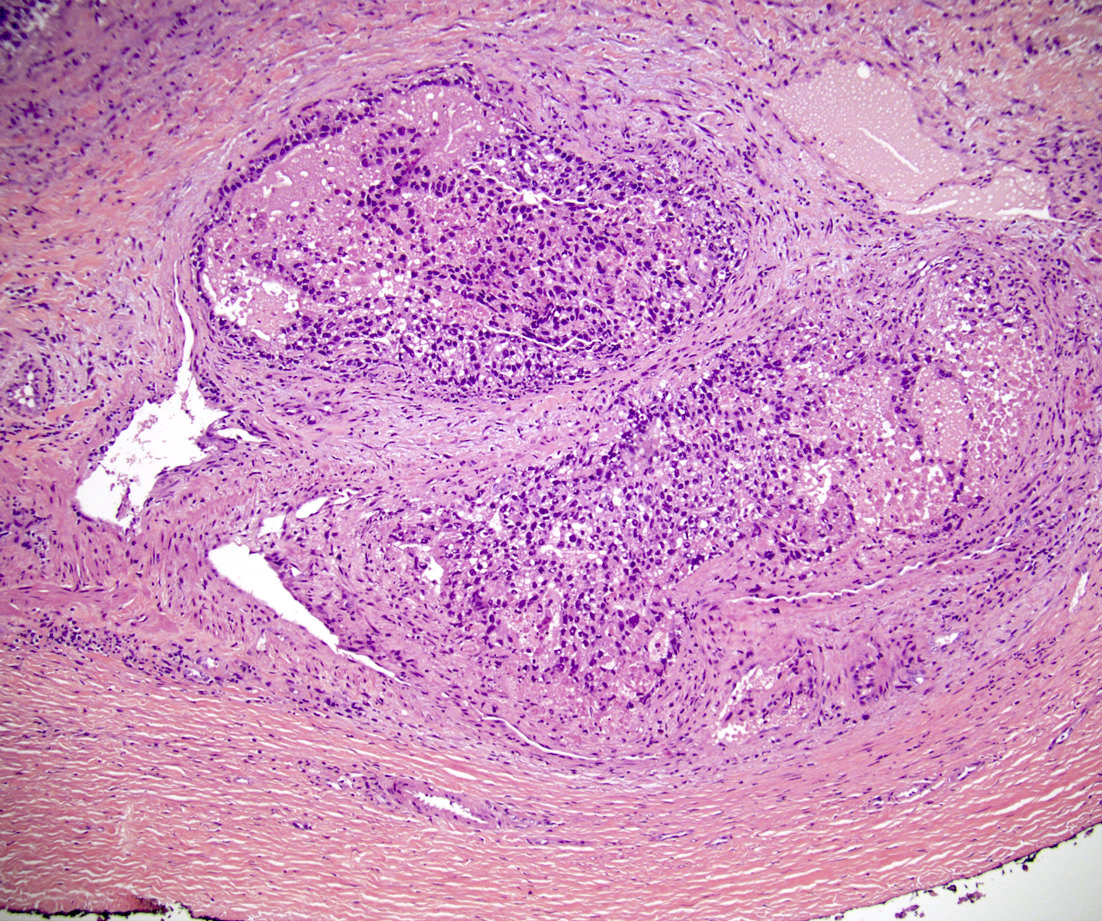

Microscopic (histologic) images

Board review style question #1

In a postpubertal testicular germ cell tumor, lymphovascular (shown above), hilar fat, epididymal and tunica vaginalis invasion are all a part of which pT category?

Board review style answer #1

D. pT2. Lymphovascular, hilar fat, epididymal and tunica vaginalis invasion are all a part of the pT2 category for testicular germ cell tumors. Lymphovascular invasion by embryonal carcinoma is shown in the image.

Comment Here Reference: